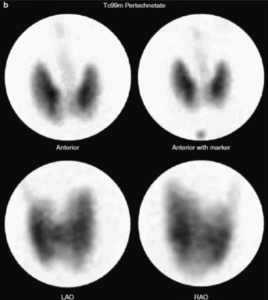

L’esame chiave per distinguere tra adenoma tossico e MTG è la scintigrafia tiroidea che utilizza radioisotopi come il tecnezio-99m o lo iodio-123, che vengono captati dalle cellule tiroidee.

Nell’adenoma tossico, come già detto, mostra un aumentato uptake nel nodulo iperfunzionante e un ridotto uptake nel resto della ghiandola (pattern “caldo” con soppressione del tessuto circostante).

Nel caso di MTG si evidenzia un pattern eterogeneo, con multiple aree di ipercaptazione corrispondenti ai noduli iperfunzionanti e aree di ipocaptazione nel tessuto non interessato.